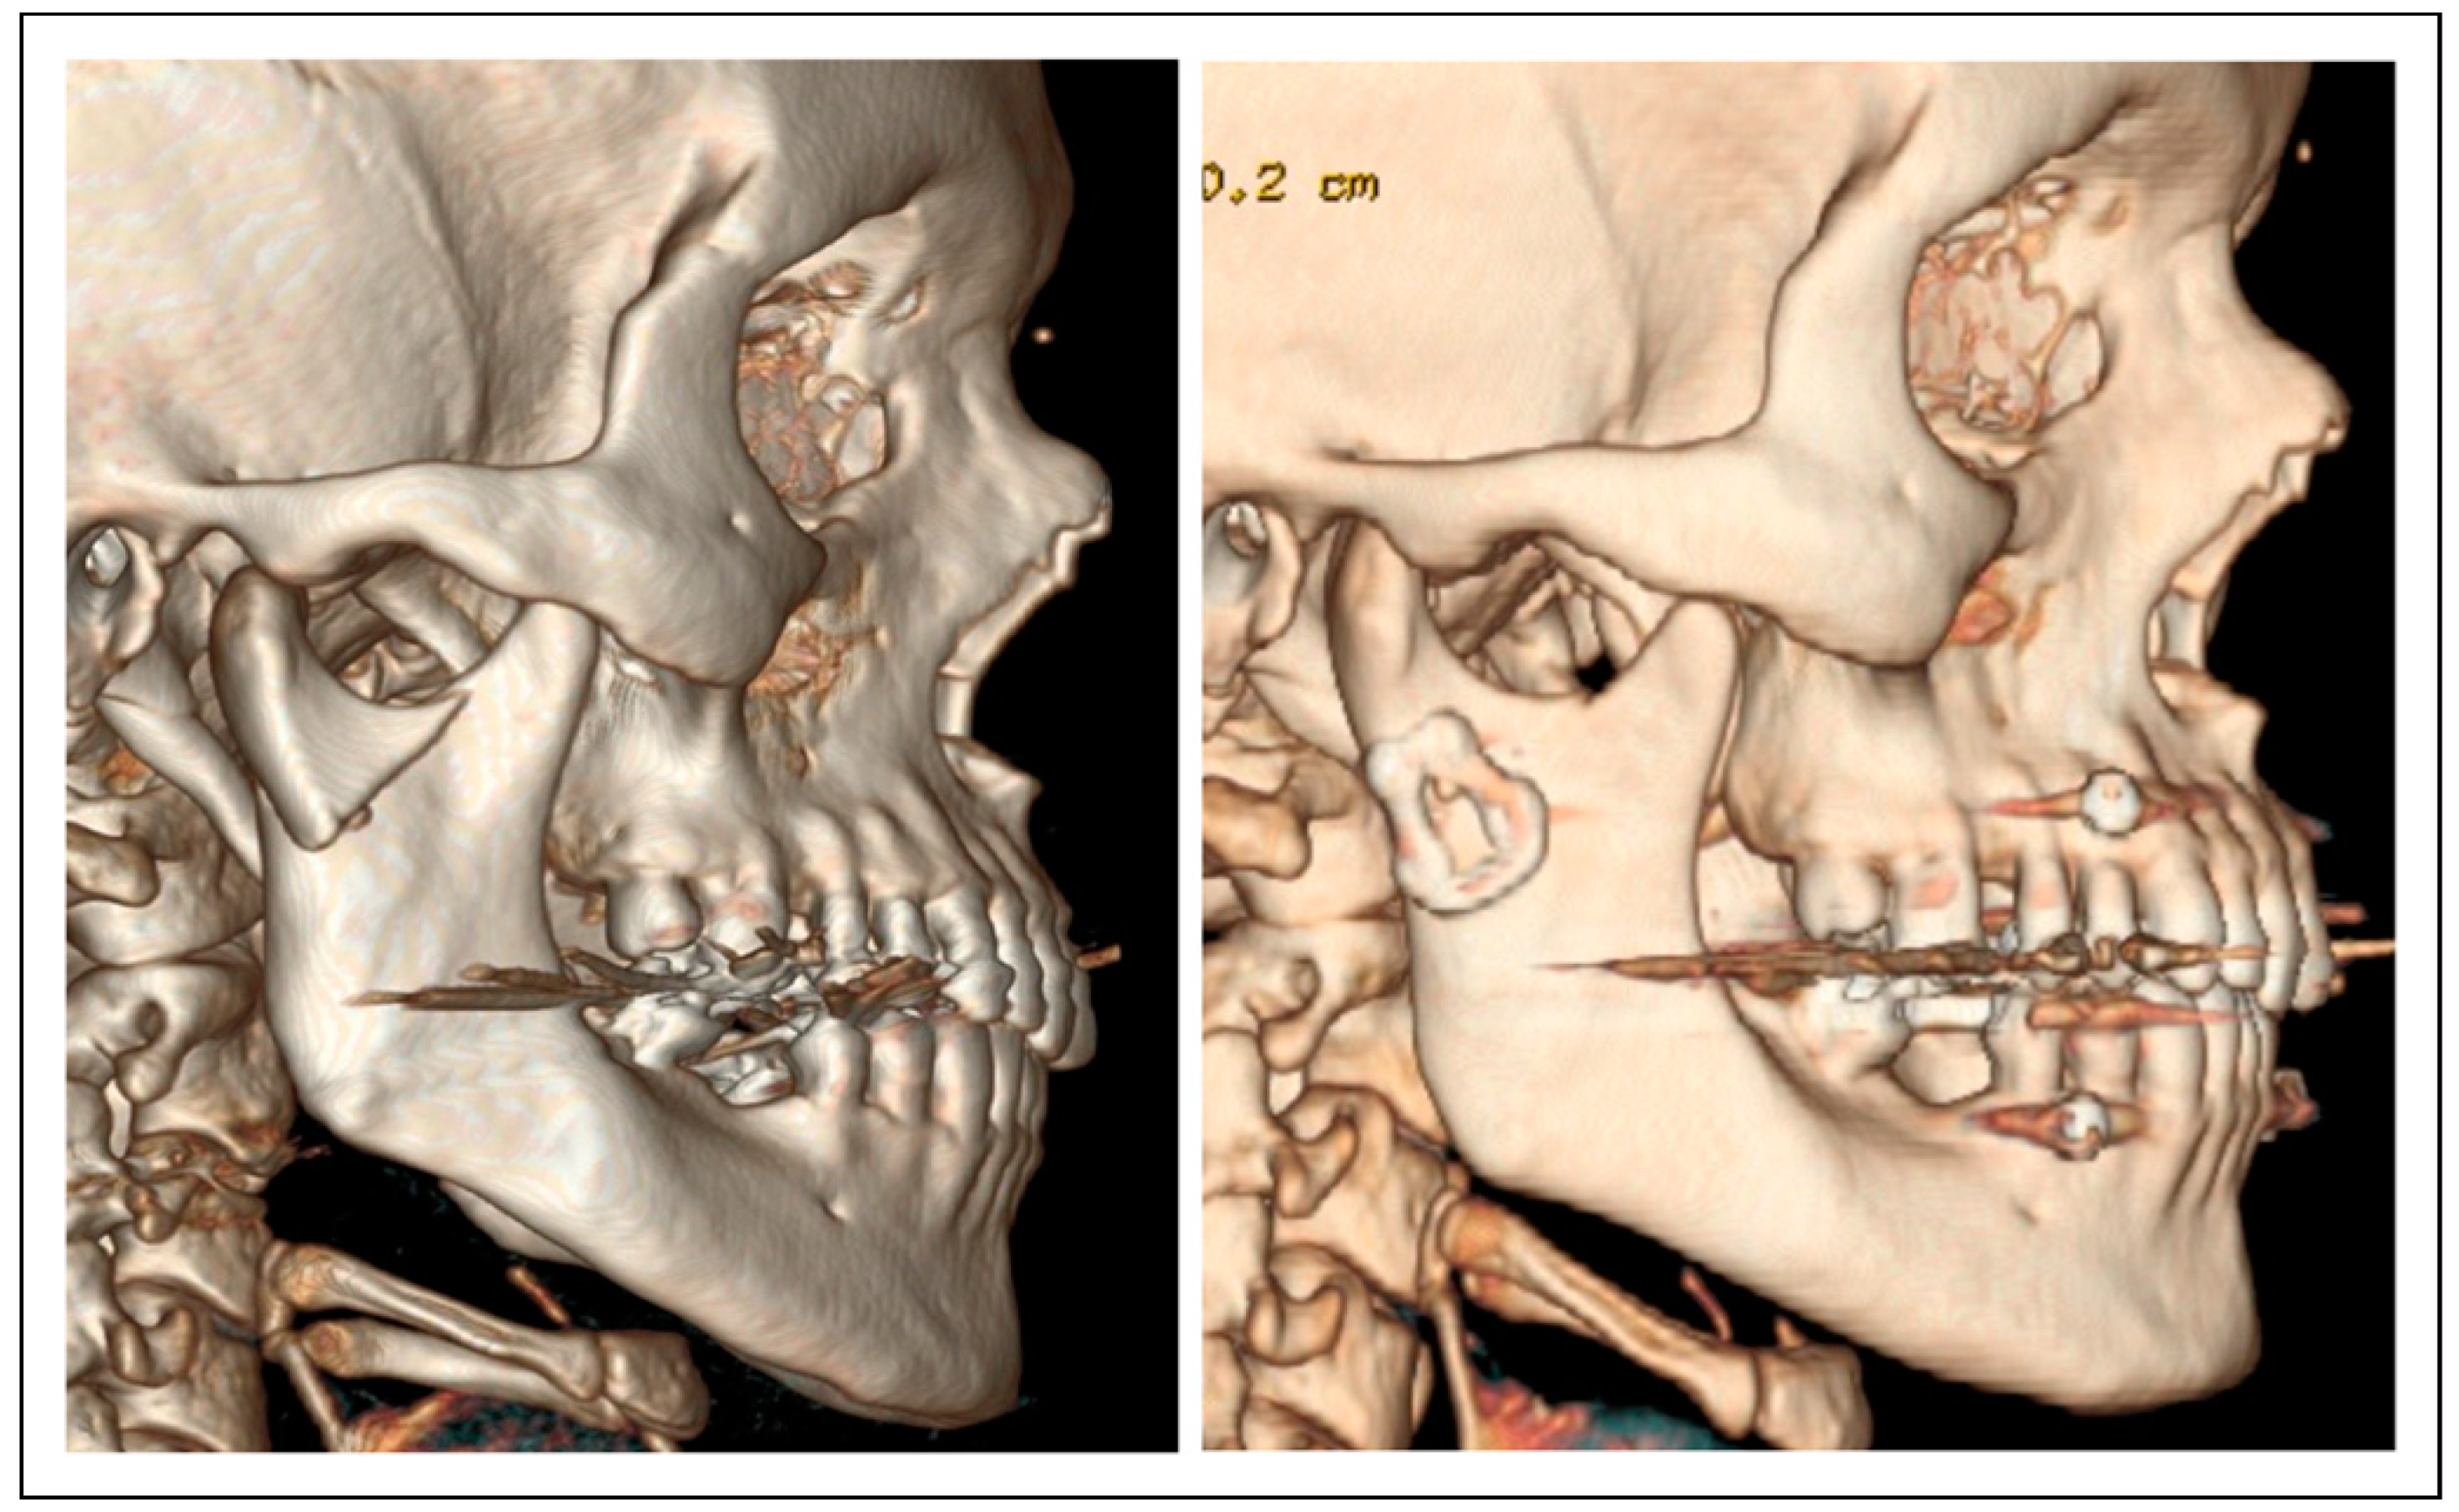

Clinical Experience with a Less Invasive Surgical Transparotid Approach and Trapezoidal Plate for Neck and Base Condylar Fractures: A Retrospective Study

Patients and Methods